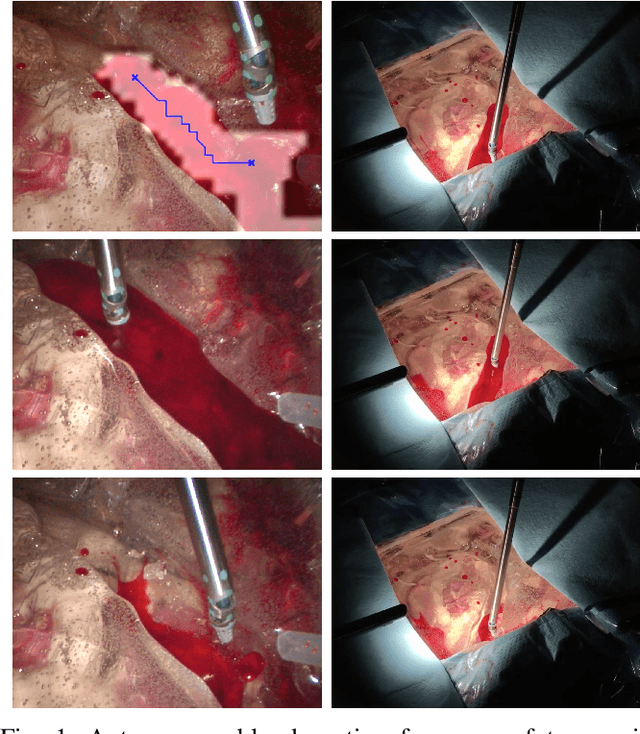

Abstract:Autonomous robotic surgery has seen significant progression over the last decade with the aims of reducing surgeon fatigue, improving procedural consistency, and perhaps one day take over surgery itself. However, automation has not been applied to the critical surgical task of controlling tissue and blood vessel bleeding--known as hemostasis. The task of hemostasis covers a spectrum of bleeding sources and a range of blood velocity, trajectory, and volume. In an extreme case, an un-controlled blood vessel fills the surgical field with flowing blood. In this work, we present the first, automated solution for hemostasis through development of a novel probabilistic blood flow detection algorithm and a trajectory generation technique that guides autonomous suction tools towards pooling blood. The blood flow detection algorithm is tested in both simulated scenes and in a real-life trauma scenario involving a hemorrhage that occurred during thyroidectomy. The complete solution is tested in a physical lab setting with the da Vinci Research Kit (dVRK) and a simulated surgical cavity for blood to flow through. The results show that our automated solution has accurate detection, a fast reaction time, and effective removal of the flowing blood. Therefore, the proposed methods are powerful tools to clearing the surgical field which can be followed by either a surgeon or future robotic automation developments to close the vessel rupture.